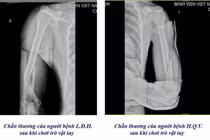

Qua thăm khám lâm sàng kết hợp chẩn đoán hình ảnh, các bác sĩ xác định bệnh nhi gãy kín 1/3 dưới hai xương cẳng tay trái - một dạng chấn thương thường gặp ở lứa tuổi thiếu niên do xương đang trong giai đoạn phát triển, mật độ xương chưa hoàn toàn hoàn thiện.

Tại khoa Ngoại tổng hợp và Liên chuyên khoa, các bác sĩ đã tiến hành gây mê, kéo nắn chỉnh lại trục xương và bó bột cố định nhằm đảm bảo phục hồi đúng giải phẫu, ngăn ngừa biến chứng lệch trục hoặc hạn chế vận động sau này. Hiện tại bệnh nhi đã điều trị ổn định và ra viện, bác sĩ đã hẹn lịch tái khám trong vài ngày tới.

Bệnh nhi 13 tuổi gãy hai xương cẳng tay khi đá bóng - Ảnh BVCC